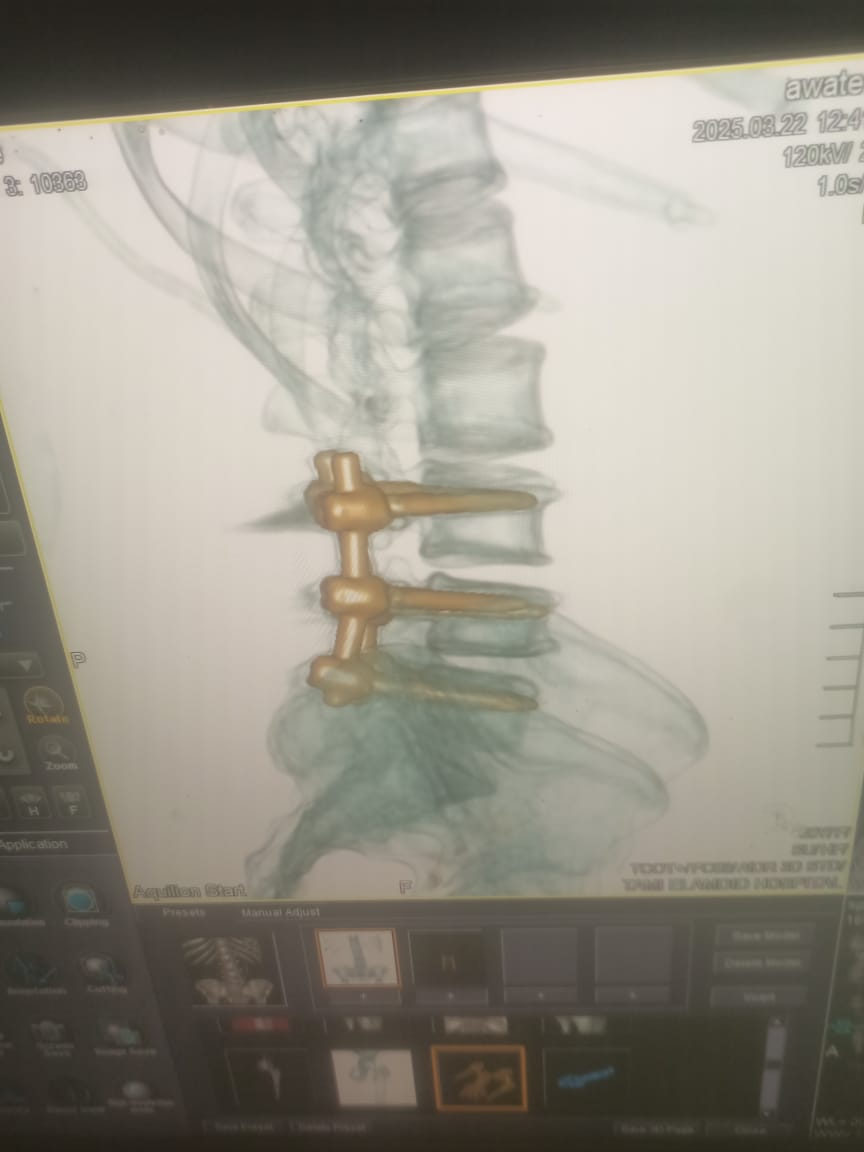

وأضاف وكيل الوزارة، أن المريضة تبلغ من العمر 45 عاما وقد حضرت إلى المستشفى وهى تعانى من سقوط فى القدم وصعوبة شديدة ف الحركة وعدم تحكم فى البول بالإضافة إلى الالام شديدة فى الظهر وعقب إجراء الفحوصات اللازمة تبين وجود عدد 2 غضروف قطنى احدهما منفجر بين الفقرات القطنيه الثالثه والرابعه والرابعه والخامسه وبناء عليه احتاجت المريضه إلى تدخل طارئ تم على إثره استئصال الغضروفين وتثبيت الفقرات القطنية بواسطة6 مسامير وشريحتين وتوسيع القناة العصبية.

وأوضح وكيل الوزارة ، بأن العملية تعد من الجراحات ذات المهارة حيث تم تم استخراج الشظية من العمود الفقري عند الفقرة T8 مع تثبيت كسر الفقرات بشريحتين و ١١ مسمار لافتا إلى حرص صحة الدقهلية على التوسع في تقديم الخدمات الطبية المتخصصة، ورفع كفاءة المستشفيات لضمان تقديم رعاية صحية متميزة للمرضى، .